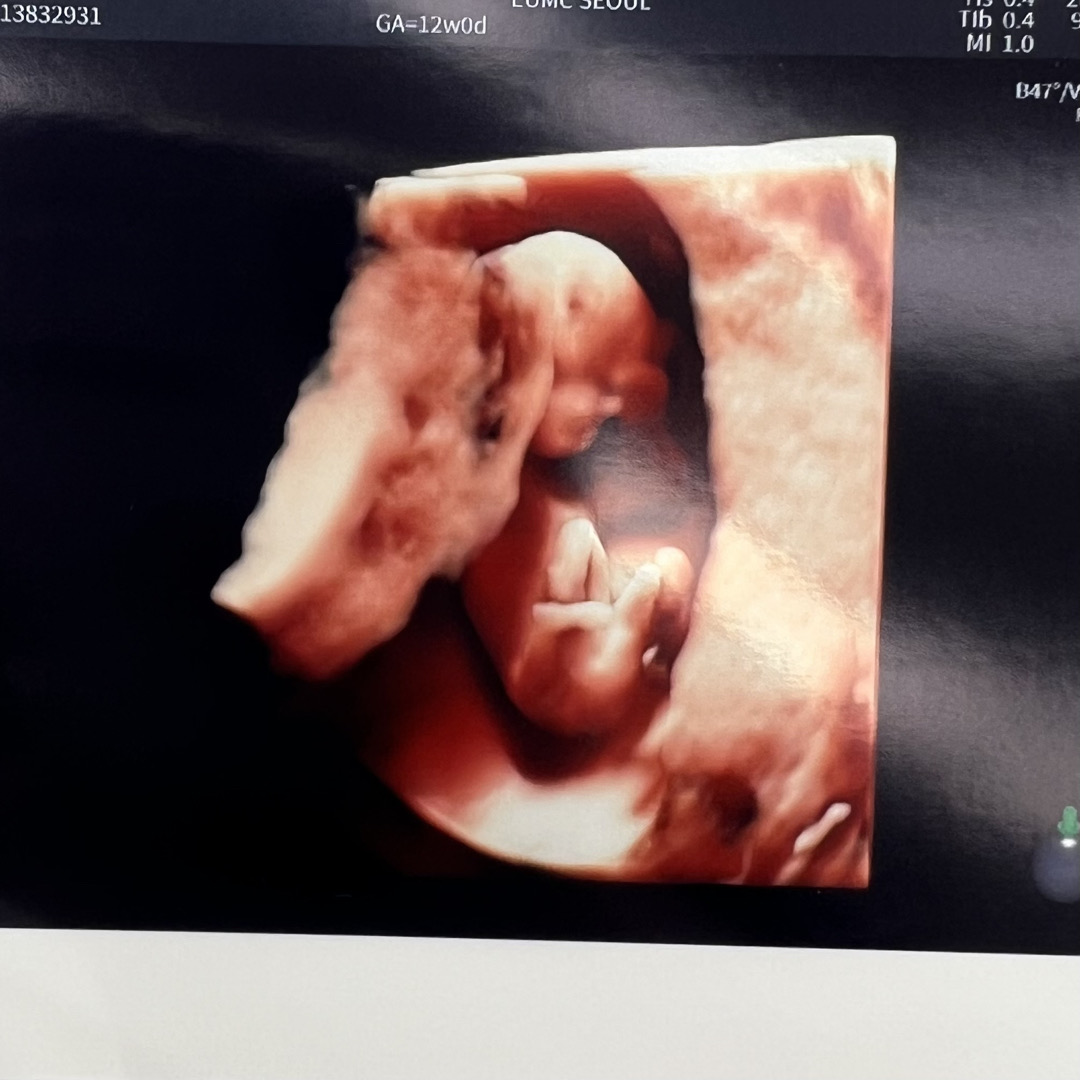

12주 입체초음파(3주사이 엄청 컸네요)

9주차에 젤리곰 보고 와서, 12주차까지 기다리며 불안하기도 했지만 임신증상(입덧과 가슴통증)이 심해 잘 있겠거니 하며 기다렸어요 난임병원에서 니프티 할 예정이라 대학병원에서 간단한 기형아검사 해주셨는데 (목투명대/좌우혈류 등등) 기초적인 것들은 문제없음으로 나와 이제사 안심이 되네요 훌쩍 커있는 아기모습 보니 이제 제법 임신이 실감이 납니다 임신 중기쯤엔 컨디션 꼭 돌아온다고 하니 힘든 초기를 보내고 있는 임산부분들. 우리 모두 힘내요💕